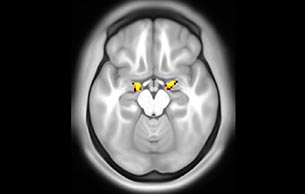

Emotional n-back task combines a test of working memory with the use of emotive (faces) and neutral (places) images. The contrast in the images is between the activity when faces are presented compared to places, showing activation in the amygdala, fusiform, and occipital face areas.

Processing based on the Human Connectome Project (HCP) pipelines. The high resolution of the fMRI data allows extraction of the cortical surface, with minimal averaging of non-cortical signal. Surface based analysis provides improved cross-subject alignment, and prevents signal contamination between adjacent sulci.

Group analysis of 88 9- and 10-year olds part of ABCD, all scanned at UVM on Philips Achieva 3.0T dStream. Scale runs from red p=0.001 to yellow p<10ˆ-5. Images provided by Dr. Watts.

Acquisition using the ABCD protocol for fMRI with TR 800 ms, TE 30 ms, flip angle 52°, 2.4 mm isotropic imaging resolution with a 216×216×144 mm3 field of view using a MultiBand acceleration factor of 6 (60 slices, no gap). Two runs of 5 minutes per subject.